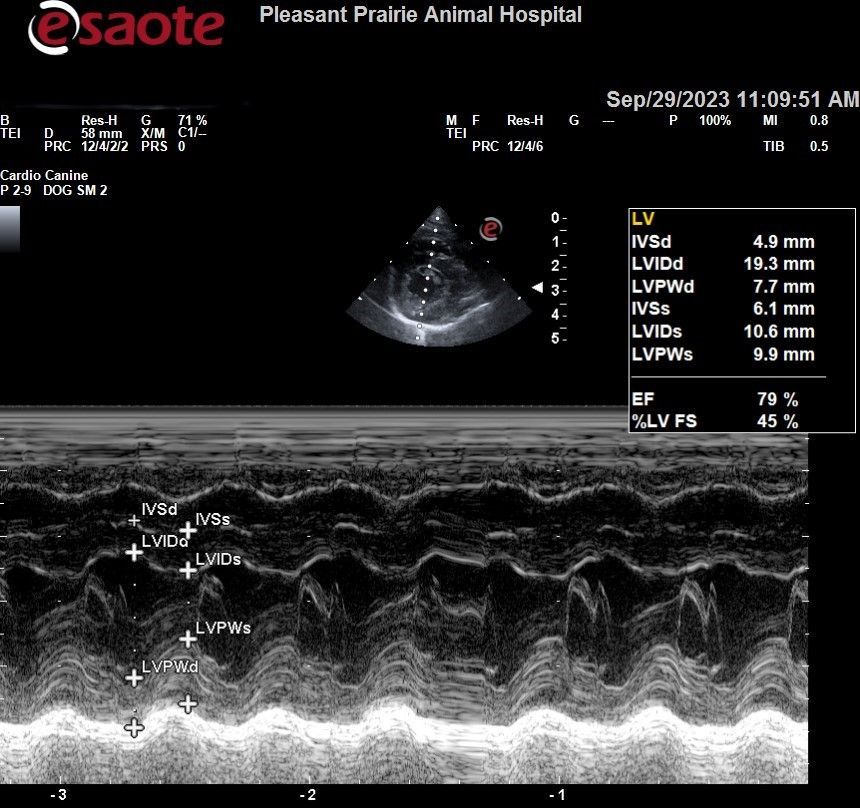

Echocardiogram (Cardiac Ultrasound)

- Used to evaluate heart size and functionality, including:

- Wall thickness

- Chamber sizes

- Contraction strength